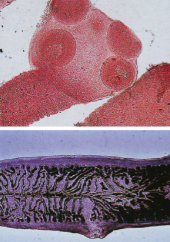

Describe the morphology of a cestode (tapeworm)

Head = Scolex for attachment

Body= Proglottids (segments) / Strobili (chain)

What is the specimen shown?

Taenia solium

Taenia saginata

What is shown

Diphyllobothrium latum

(Fish Tapeworm)

What is shown?

Dipylidium caninum